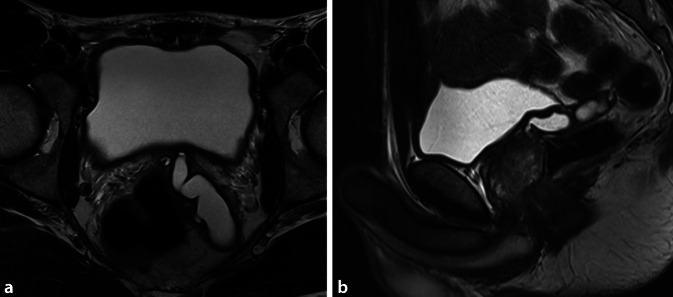

29岁男性原发不孕症2年提出进一步评估。重复精子图显示无精子症和酸性ph值。超声检查显示两睾丸大小和实质正常,但双侧输精管未触及。磁共振显示左侧输精管囊性扩张,左侧精囊扩张。右侧输精管未见。睾丸精子提取(TESE)成功,仅显示精子发生轻微损伤,约翰逊评分为9分。

A 29-year-old man with primary infertility for 2 years presented for further evaluation. Repeated spermiograms showed azoospermia and an acidic pH. Sonographically, both testes showed normal size and parenchyma, but the vas deferens was bilaterally not palpable. Magnetic resonance imaging showed a cystically dilated left vas deferens and a dilated left seminal vesicle. The right vas deferens could not be visualized. Testicular sperm extraction (TESE) was successful and showed only slight impairment of the spermatogenesis with a Johnson score of 9.